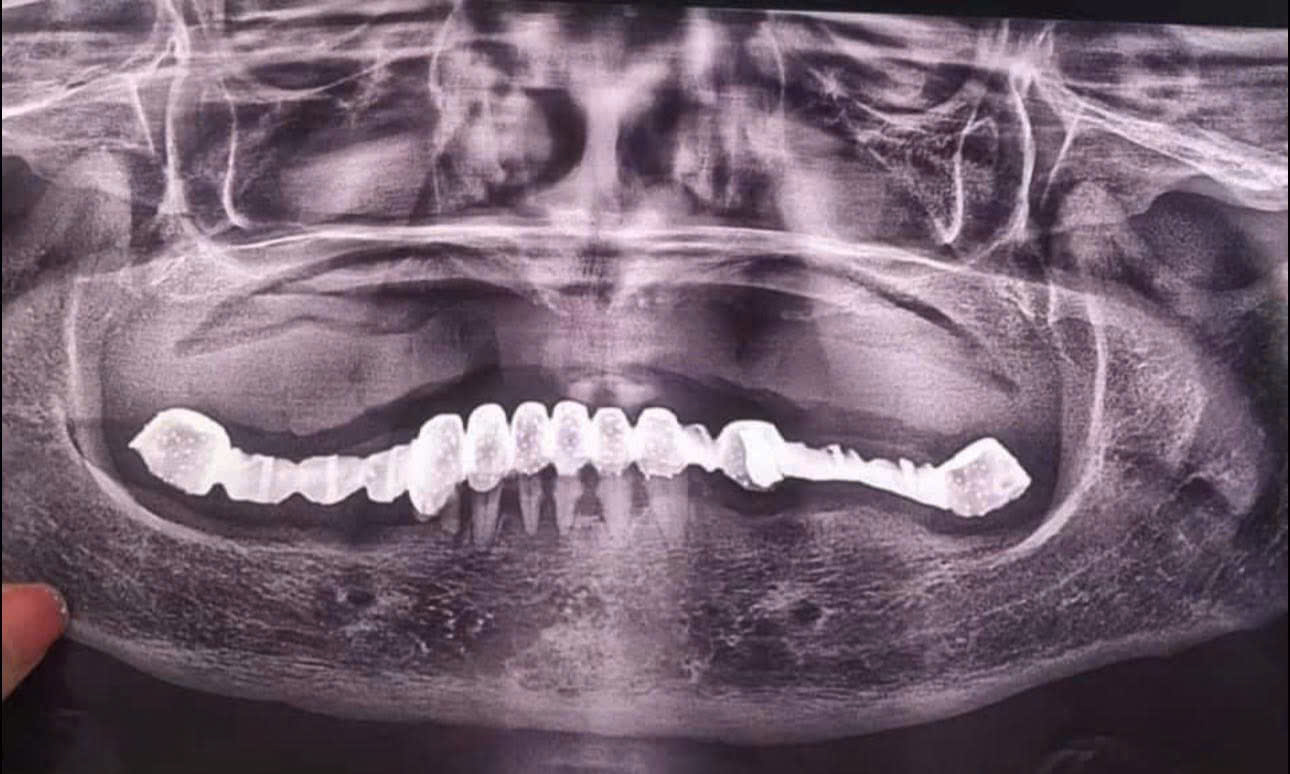

Cô khách hàng 60 tuổi quyết tâm thay đổi từ cầu răng sứ sang trồng răng Implant

Ghi chú quan trọng (đọc kỹ)